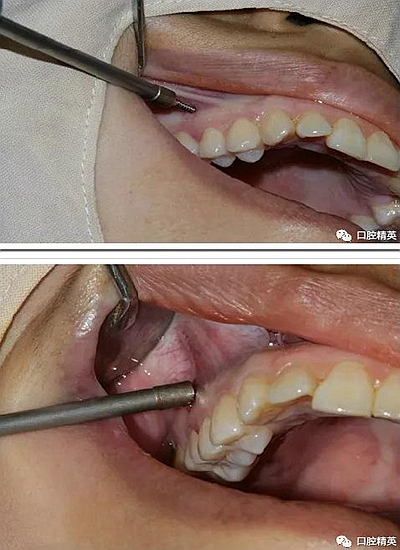

再次,植入微型種植體,在附著牙齦處不需要粘骨膜翻瓣,在牙槽黏膜處則需要切開黏膜以避免植入時(shí)軟組織被卷入,植入部位通常在膜齦結(jié)合部位或偏根方2~3mm,植入角度與骨面垂直并傾斜15~20度,即向根尖方向植入,術(shù)后拍根尖片以確認(rèn)與牙根的關(guān)系。術(shù)后口服抗生素預(yù)防感染并進(jìn)行口腔衛(wèi)生宣教。

2、助攻型種植釘,上頜與頜骨成30-40°角,下頜與頜骨成10-20°角(目的:1、降低損傷牙根及牙周膜的機(jī)率;2、使種植釘盡量植入骨皮質(zhì)內(nèi),降低松動(dòng)機(jī)率);自攻型種植釘與頜骨垂直;個(gè)人習(xí)慣:自攻型種植釘上下頜均與頜骨成30-40°角。

3 、無論是助攻型還是自攻型種植釘,植入前分離粘骨膜步驟必不可少。軟組織的夾入是手術(shù)失敗的常見原因之一。

4 、植入時(shí),旋轉(zhuǎn)速度盡量慢,防止因產(chǎn)熱過多使組織變性,影響釘骨愈合;旋入時(shí)手盡量穩(wěn),防止洞口直徑過大于種植釘直徑。